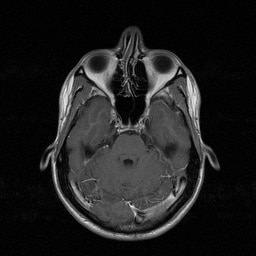

Acute Otitis Media (AOM)

Cheatsheets

1

Mnemonics

0

Images

1

Picmonic

0